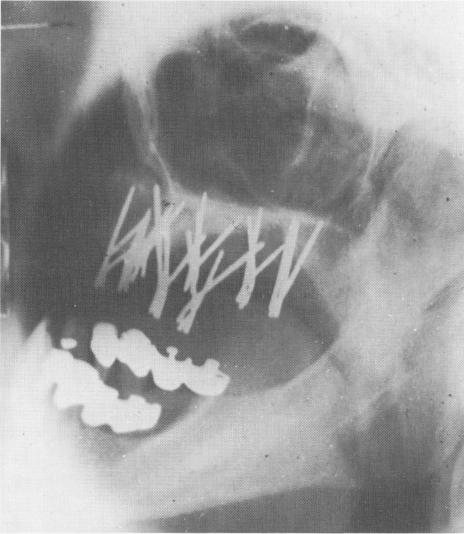

Fig. 10-217. A postoperative lateral plate roentgenogram shows the eight sections of triplants in position. (Courtesy I. Lew.)

The pins were then bent so that their ends were parallel with one another, and the excess length was cut away (Fig. 10-215). Teflon cylinders, each containing three parallel holes, were then filled with acrylic and placed over the pins to lock them together as individual tripods (Fig. 10-216). The denture was then fitted into position and a post-operative radiograph taken (Fig. 10-217).